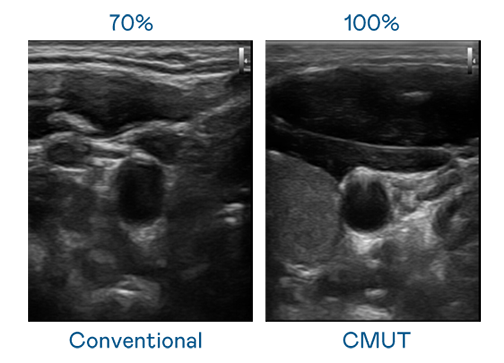

CMUT 技术是一种用电容式微机电元件来产生超音波讯号的技术。与传统 PZT 压电式技术相比,CMUT 频宽增加 30%,更宽频的超音波讯号让影像解析度大幅提升,是实现高影像品质医疗超音波扫描、促进精准医疗发展的关键技术。

超音波影像的解析度高低,首先取决于探头能发出的讯号频宽。六合联盟 CMUT 可提供高清晰的超音波讯号,提供高频宽、高灵敏度、影像纹理细节更高的超音波影像,协助医护人员缩短影像判读时间及利用精准的医疗影像进行诊断。